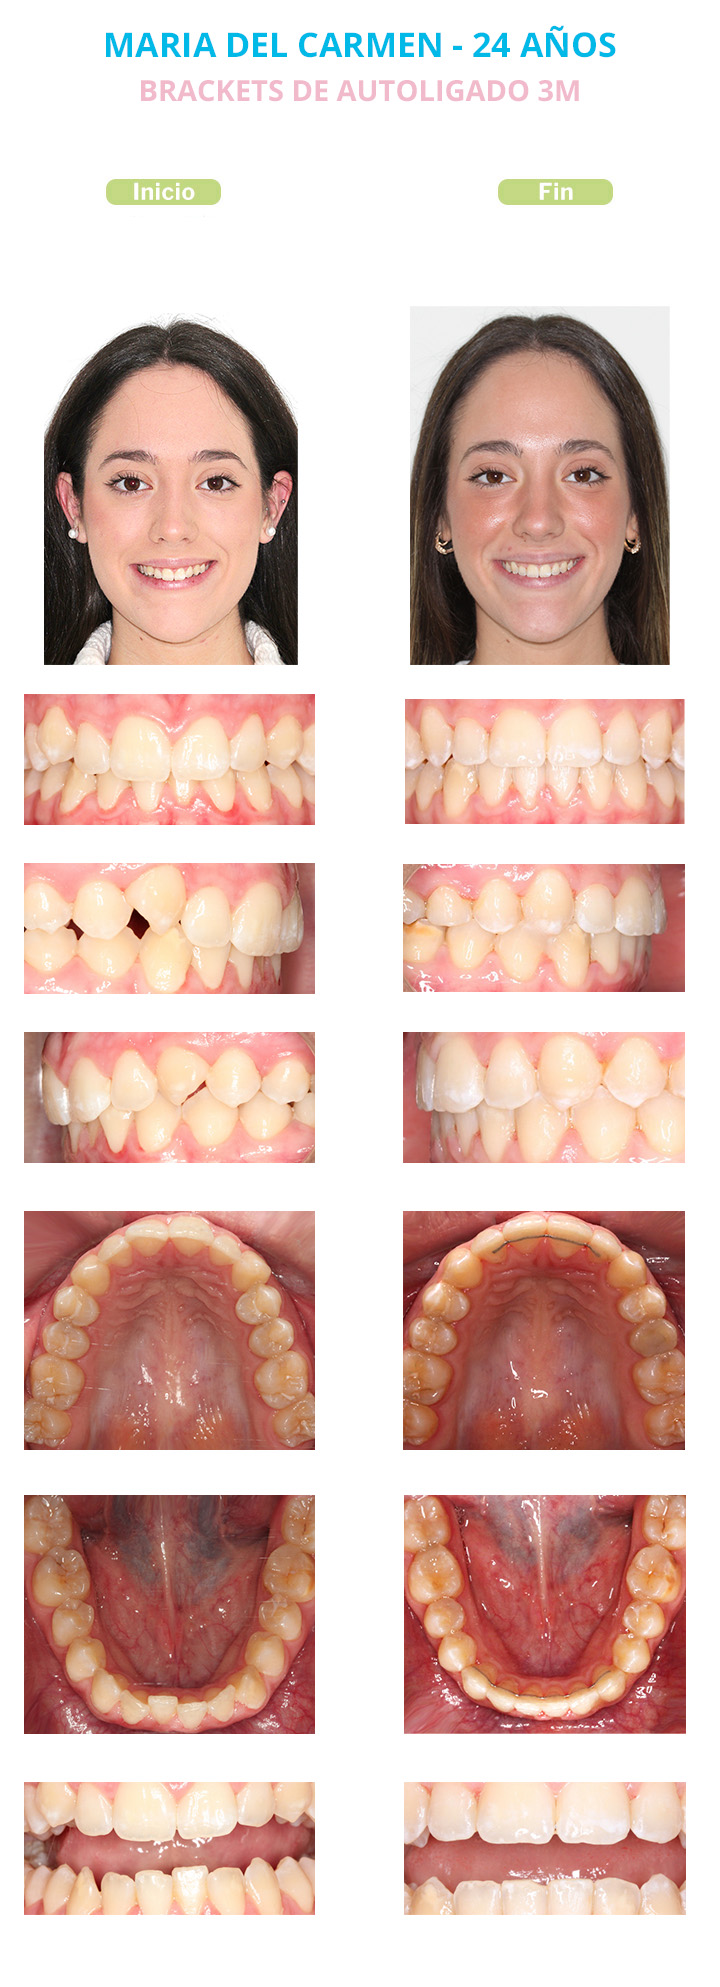

María del Carmen, 24 años

María del Carmen acudió a nuestra consulta porque quería mejorar la estética de su sonrisa y su mordida. Los dientes se los veía cada vez más apiñados no le encajaban bien y quería una solución.

Las alteraciones que presentaba María del Carmen y que teníamos que corregir eran:

- Sobremordida aumentada: Los Incisivos superiores cubrían verticalmente en exceso a los incisivos inferiores.

- Apiñamiento dentario.

- Compresión dentoalveolar superior e inferior: Ambas arcadas dentarias estaban comprimidas dando un efecto de sonrisa estrecha con espacios negros a ambos lados de la sonrisa.

- Clase II molar y canina derecha.

- Líneas medias desviadas.

- Incisivos laterales superiores estrechos.

- Caninos superiores muy rotados.

Le ofrecimos a María del Carmen los diferentes tipos de aparatos de Ortodoncia para llevar a cabo su tratamiento. Ella eligió Brackets de autoligado 3M Clarity Ultra.

Su tratamiento tuvo una duración de 23 meses.

En las fotos finales de María del Carmen se puede observar que hemos corregido con éxito todos los problemas que tenía. Hemos corregido la alteración en el engranaje de sus dientes superiores con los inferiores, logrando una correcta sobremordida. Hemos aumentado la anchura de los Incisivos laterales superiores para proporcionarles un correcto tamaño con respecto a sus dientes adyacentes. Hemos solucionado el apiñamiento que tenía, dando una correcta forma de arcadas y logrando una sonrisa amplia.

A partir de este momento María del Carmen luce una sonrisa con la firma Alba&Hernanz. Una sonrisa perfectamente alineada, amplia, estética y con una oclusión y una función perfecta.